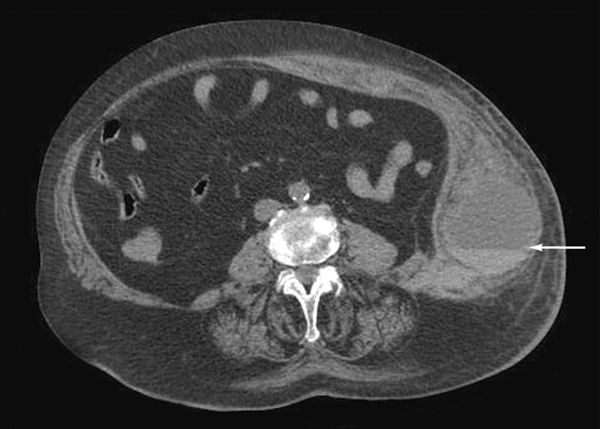

A 77-year-old woman had shortness of breath that worsens when she lies down and intermittent left flank pain. She had had mild nonbloody diarrhea, but no vomiting or oral intake intolerance, and an embolic cerebral stroke for which she takes warfarin. There is a large, firm, ecchymotic, exquisitely tender mass on her abdomen. She had fallen in her bathroom a few days earlier.

A CT scan of the abdomen and pelvis without contrast showed a massive abdominal wall hematoma arising from the left rectus sheath of the lateral abdominal wall with a fluid-blood level (hematocrit sign) consistent with an acute hemorrhage.

Female sex is a factor known to predispose to the development of an abdominal wall hematoma. Others are older age and the use of antiplatelet or anticoagulant agents.

A hematoma can present with apparent bruising and tenderness over any aspect of the abdominal wall. Patients typically do not have an underlying intra-abdominal pathology.